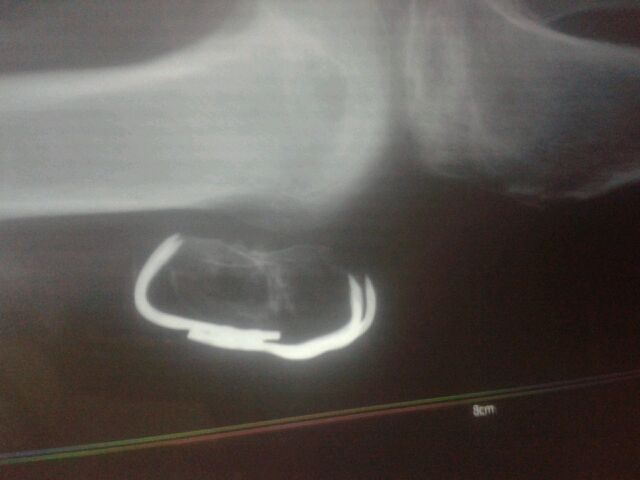

88哥,你好,麻烦你帮我看下片子,髌骨骨折,这是术后两个半月的

这是术后四个月的片子

这是昨天术后五个月的片子,怎么那条骨缝还没有长好,现在也不敢暴力锻炼,麻烦您帮我看下的,谢谢您了

属横断骨折,髌骨抓固定,愈合不是很好,但也不是骨不连。另感觉骨质不正常,发个整片看看。髌骨骨折很少发生骨不连,更少发生缺血性坏死,所以你要再问问医生,排除缺血性坏死的可能。

从这张片子看,的确不乐观,担心缺血性坏死可能的存在,也有其他导致骨质异常的可能,一定要拿片子去大医院看,给一个准确答复,如出现上述情况也别怕,有办法,最好不是。

回复 冰鉴2008 :CT有内固定效果肯定不好,但有很多办法,我具体和你说说你现在可能的情况。从X片看,骨质有问题,有三种可能:一是感染,可能性最大,也最好治;二是病理性的,如肿瘤病变发生溶骨;三是无菌性坏死。坏死,比较少见,病毒低毒性感染可以查一下血沉、CRP。